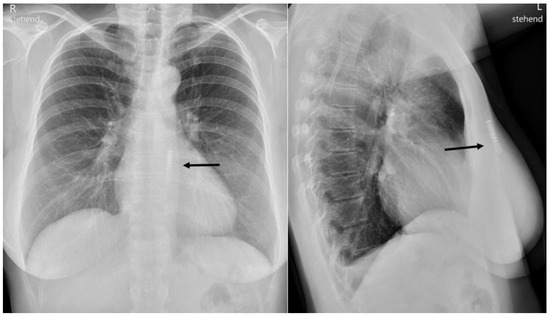

Congenital Left Ventricular Diverticulum in an Asymptomatic Patient: Multi-Modal Evaluation

by Negro Alessandro, Carballo David, Noble Stéphane and Müller Hajo

Congenital left ventricular diverticula are rare cardiac malformations. Few data are available regarding their prevalence, which is estimated to be around 0.04% and 0.7%, according to retrospective series. In our case a diverticular apical lesion of the left ventricle was incidentally found on [...] Read more.

Congenital left ventricular diverticula are rare cardiac malformations. Few data are available regarding their prevalence, which is estimated to be around 0.04% and 0.7%, according to retrospective series. In our case a diverticular apical lesion of the left ventricle was incidentally found on an urgent thoracic computed tomography scan, performed to rule out abdominal aortic rupture. A thorough evaluation with echocardiography, coronary angiography, ventriculography and cardiac magnetic resonance imaging was performed. After discussion in our heart team, which took into consideration the lack of cardiac symptoms, the small size of the diverticulum and the absence of thrombus, we decided on a conservative option. Full article